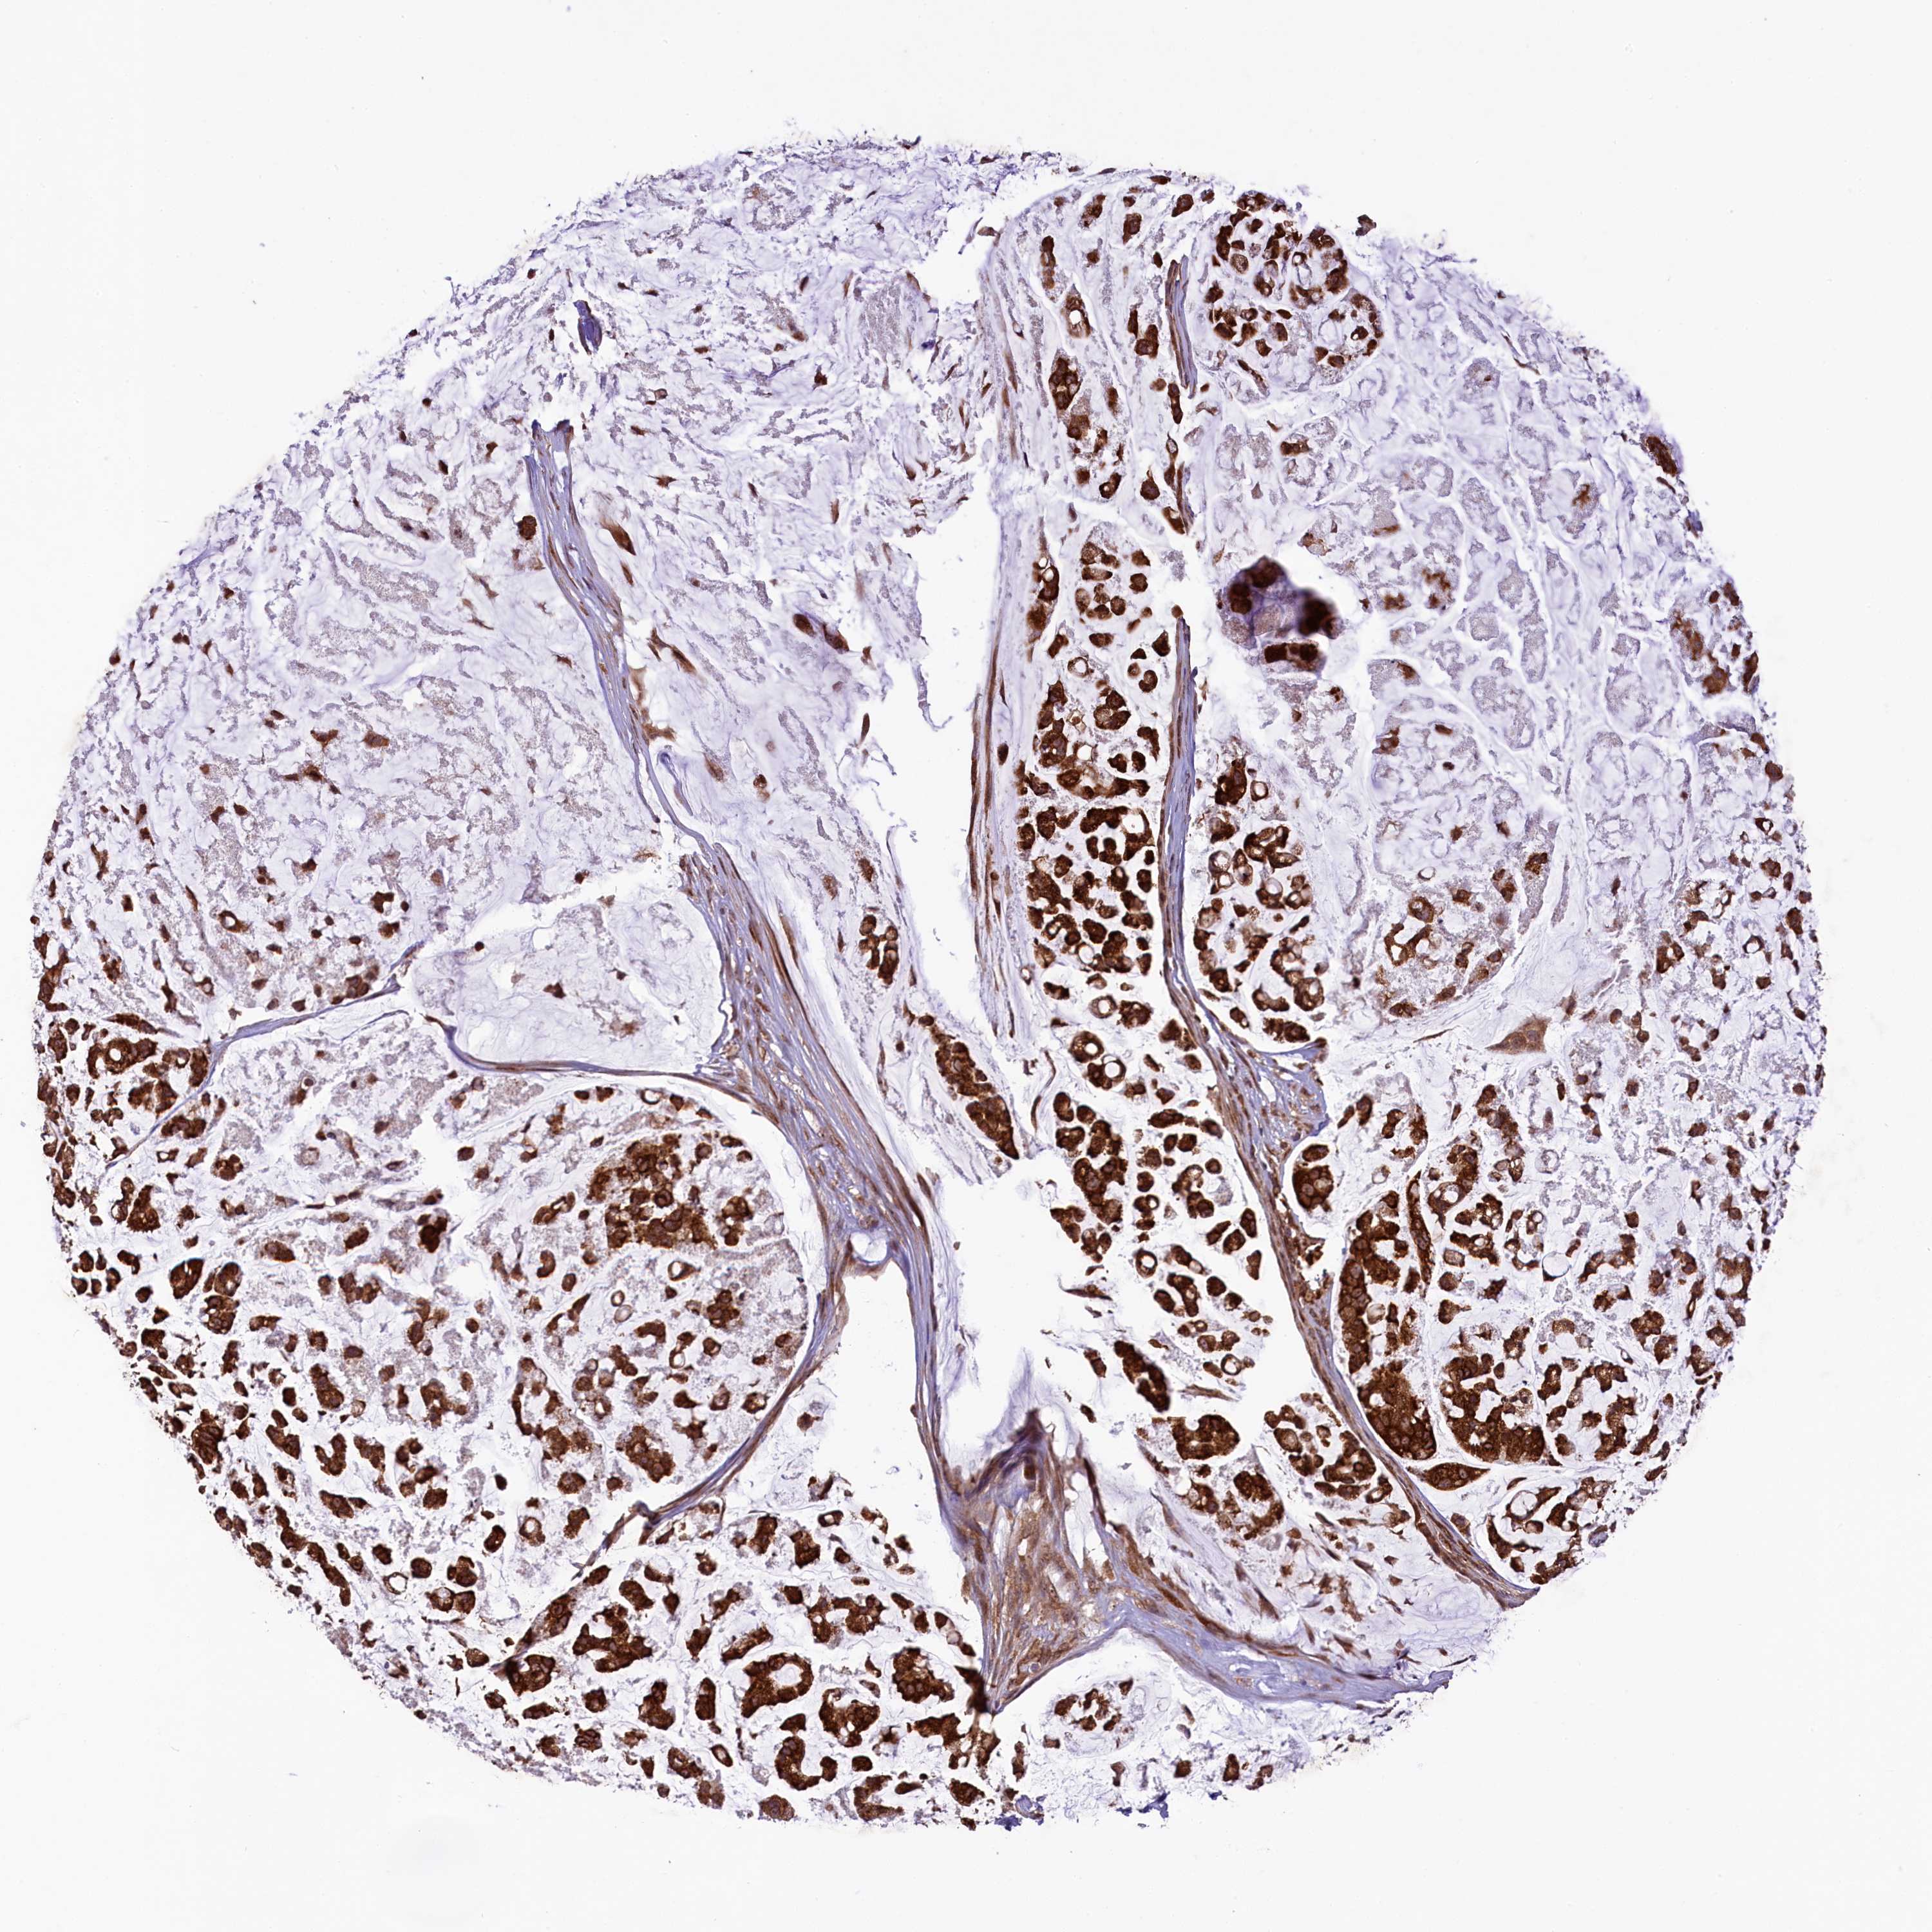

STOMACH CANCER - Protein expressioni

A mouse-over function shows sample information and annotation data. Click on an image to view it in a full screen mode. Samples can be filtered based on level of antibody staining by selecting one or several of the following categories: high, medium, low and not detected. The assay and annotation is described here.

Note that samples used for immunohistochemistry by the Human Protein Atlas do not correspond to samples in the TCGA dataset.

Antibody stainingi

Antibody staining in the annotated cell types in the current human tissue is reported as not detected, low, medium, or high, based on conventional immunohistochemistry profiling in selected tissues. This score is based on the combination of the staining intensity and fraction of stained cells.

Each image is clickable and will lead to virtual microscopy that enables deeper exploration of all samples and also displays staining intensity scores, fraction scores and subcellular localization as well as patient and tissue information for each sample.

Antibody HPA039306

Antibody HPA039673

Staining

High

Medium

Low

Not detected

Intensity

Strong

Moderate

Weak

Negative

Quantity

>75%

75%-25%

<25%

None

Location

Nuclear

Cytoplasmic/membranous

Cytoplasmic/membranous,nuclear

Adenocarcinoma, NOS